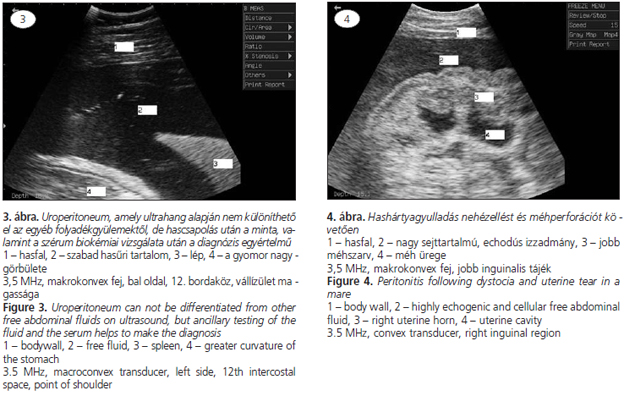

A vizsgálatot szisztematikusan (caudocranialisan és dorsoventralisan) célszerű elvégezni. A transabdominalisan elvégzett vizsgálat során azonosítható a szabad hasűri folyadék megléte, helye, kiterjedése. A folyadék jellegére (transsudatum, vér, vizelet, szeptikus izzadmány), annak echogenitása alapján, szintén következtethetünk (1., 2., 3. és 4. ábra). A vizsgálat során azonosíthatóak a fibrinlerakódások, a tályogok, az adhéziók, az ileusos bélszakaszok is (2, 3). Hascsapolás és drén behelyezése során megkereshető a ventralis hasfal azon pontja, ahol a legmagasabb a folyadékoszlop.

A kétdimenziós B-mód ultrahangvizsgálat kiválóan alkalmas vizsgálati módszer a betegség diagnosztizálására, valamint ultrahangárnyékban elvégzett hascsapolásra vagy drén behelyezésére. A vizsgálathoz az állatot nem feltétlenül szükséges borotválni, amennyiben a szőr megfelelően rövid. A jobb kontaktus érdekében izopropil-alkohol vagy metilcellulóz gél használható. A vizsgálatot lineáris, makro- és mikrokonvex transzducerrel is végezhetjük. Felnőtt ló esetében 2–4, csikóknál 3,5–5 MHz az ideális frekvencia, ami 15–35 cm mélységű szöveti penetrációt tesz lehetővé.